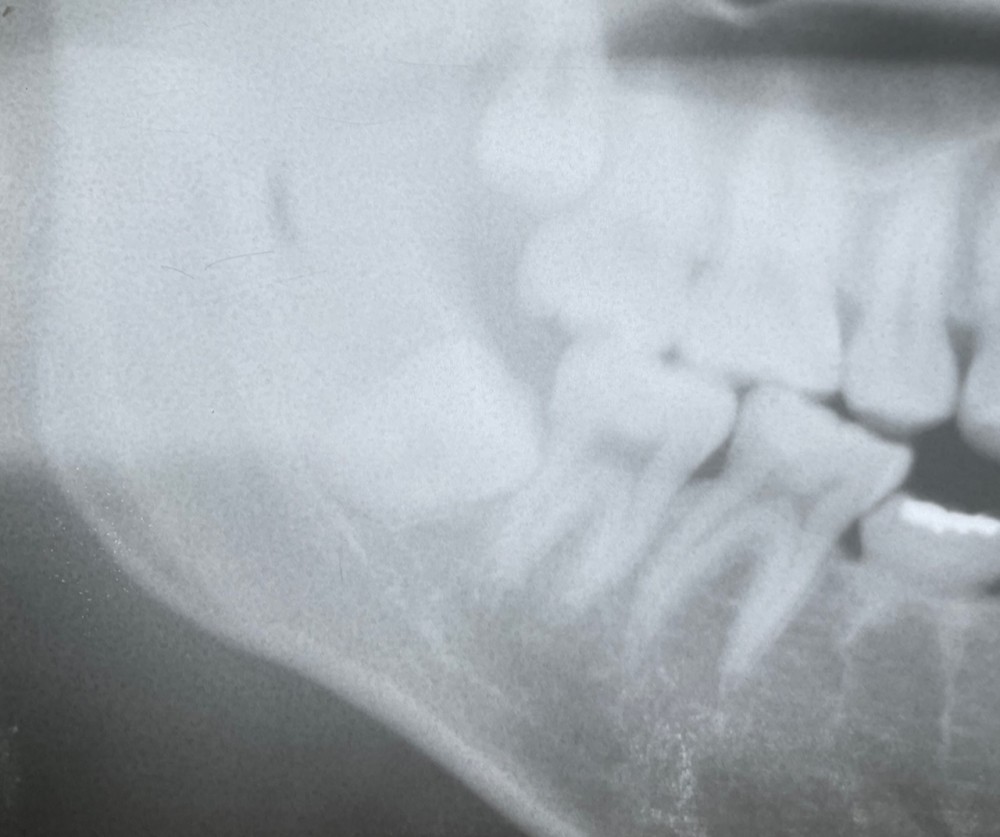

その約1週間後にも、再びスポーツで同じ場所をぶつけて、痛みがあると言うことで、再度来院されました。

その際のエックス線写真がこちらです。

骨折の線が、黒いラインとして見えるのがわかります。

総合病院の口腔外科に紹介させていただきました。

精密検査の結果、手術ではなく、自然治癒を待つことになりました。